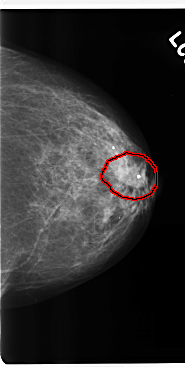

FILE: C_0206_1.LEFT_CC.OVERLAY

TOTAL_ABNORMALITIES 1

ABNORMALITY 1

LESION_TYPE MASS SHAPE IRREGULAR MARGINS SPICULATED

ASSESSMENT 4

SUBTLETY 5

PATHOLOGY MALIGNANT

TOTAL_OUTLINES 1

BOUNDARY

LEFT_CC LINES 4792 PIXELS_PER_LINE 2400 BITS_PER_PIXEL 12 RESOLUTION 50 OVERLAY